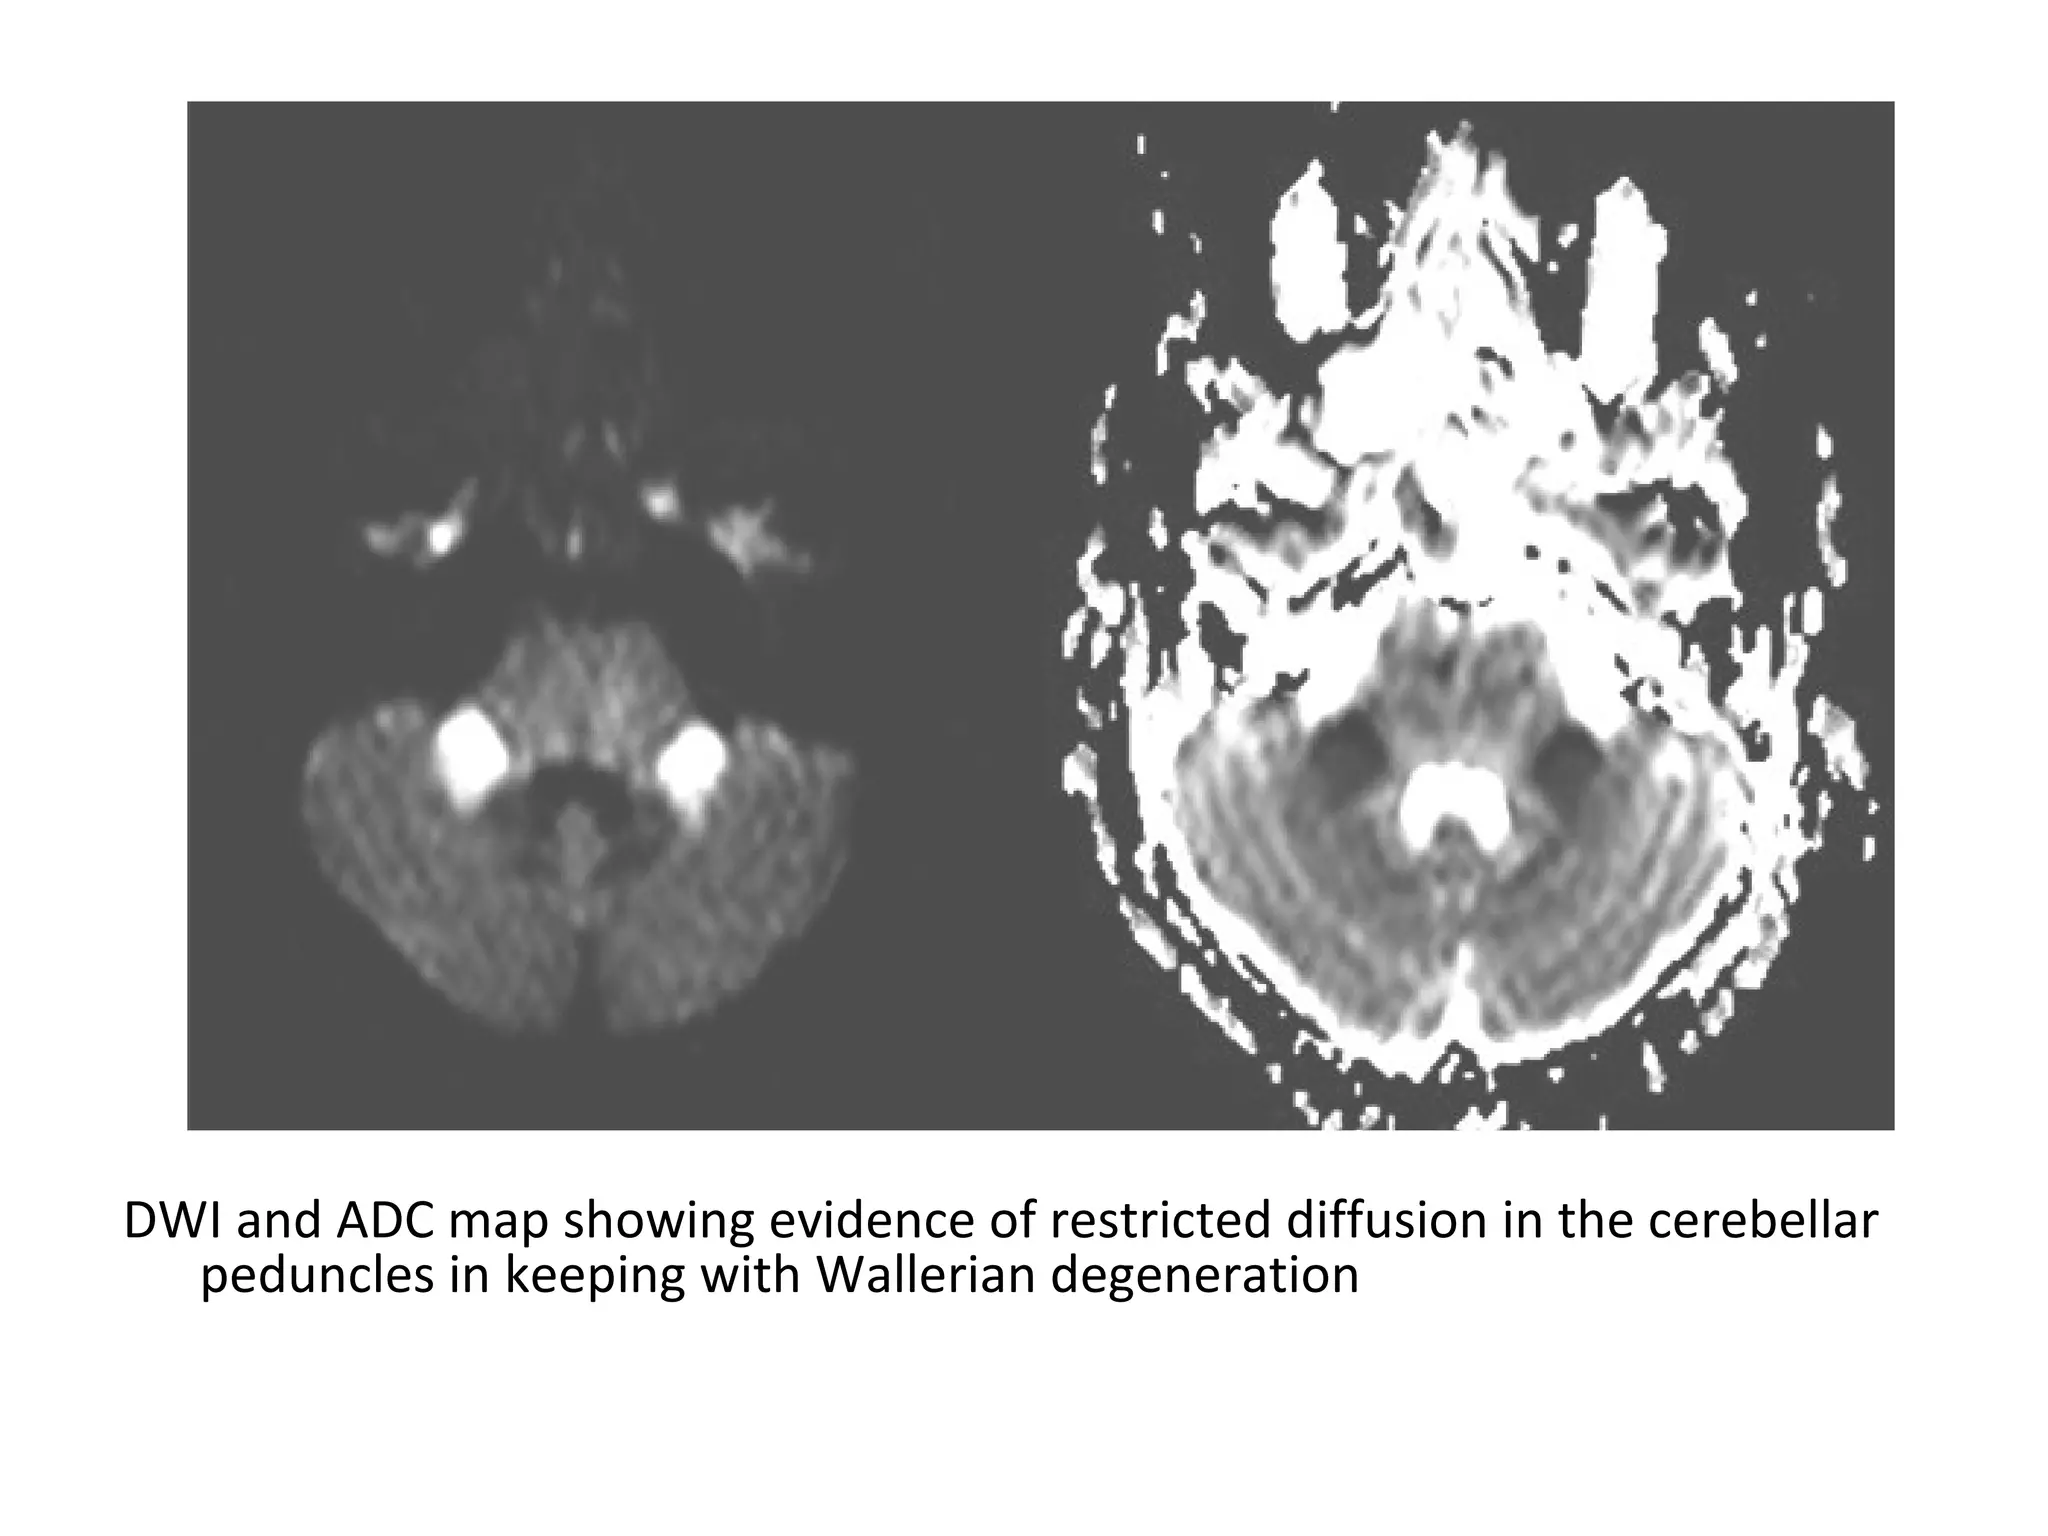

Axial T2 (A) shows symmetrical hyperintense signal in both the MCPs

(arrow) , Few hyperintense foci are also seen in pons , Diffusion (B) shows

hyperintense signal in both MCPs and in right paramedian pons ,

Corresponding ADC map (C) reveals reduced signal suggestive of restricted

diffusion

DWI and ADC map showing evidence of restricted diffusion in the cerebellar

peduncles in keeping with Wallerian degeneration